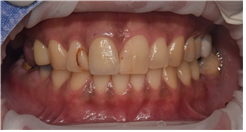

치료 전